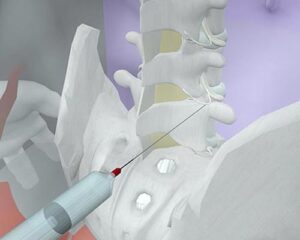

Os bloqueios ou infiltrações são procedimentos minimamente invasivos nos quais um medicamento é injetado diretamente na área alvo para fornecer